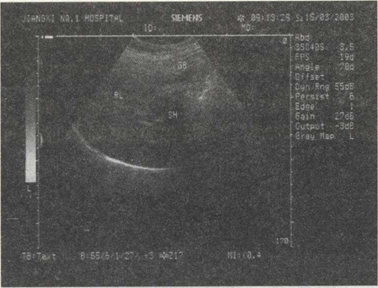

32.女,42岁,反复上腹疼痛不适多年,加重3天。声像图如图所示,最可能的诊断为()